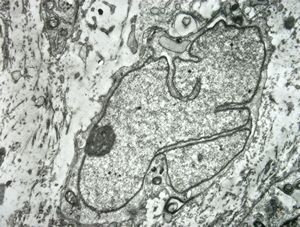

M,15y. | neurinoma n. optici